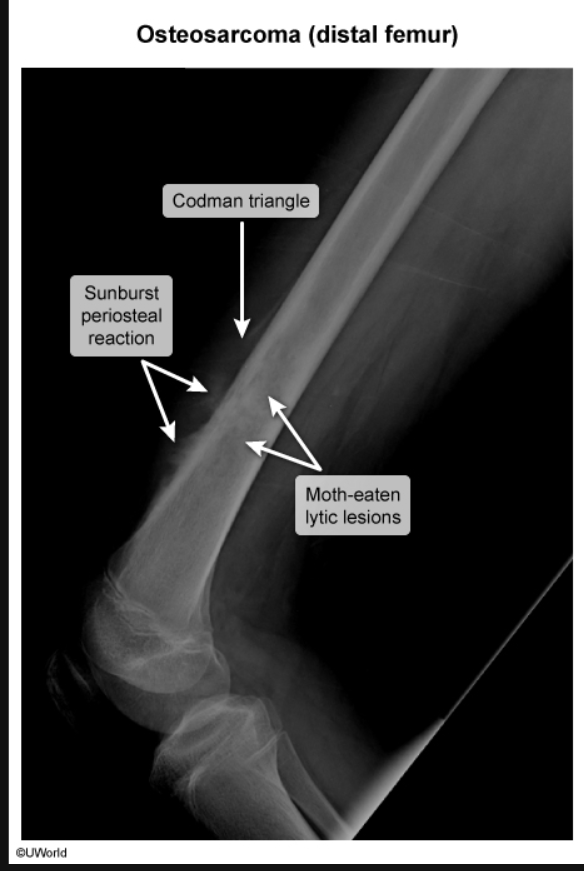

Radiologic findings of Osteosacrcoma

Radiographic findings of osteosarcoma include destruction of the normal trabecular bone pattern, mixed radiodense (sclerotic) and radiolucent (lytic) areas, and periosteal new bone formation with lifting of the periosteum (Codman triangle). Adjacent soft tissue often demonstrates ossification in a “sunburst” pattern.